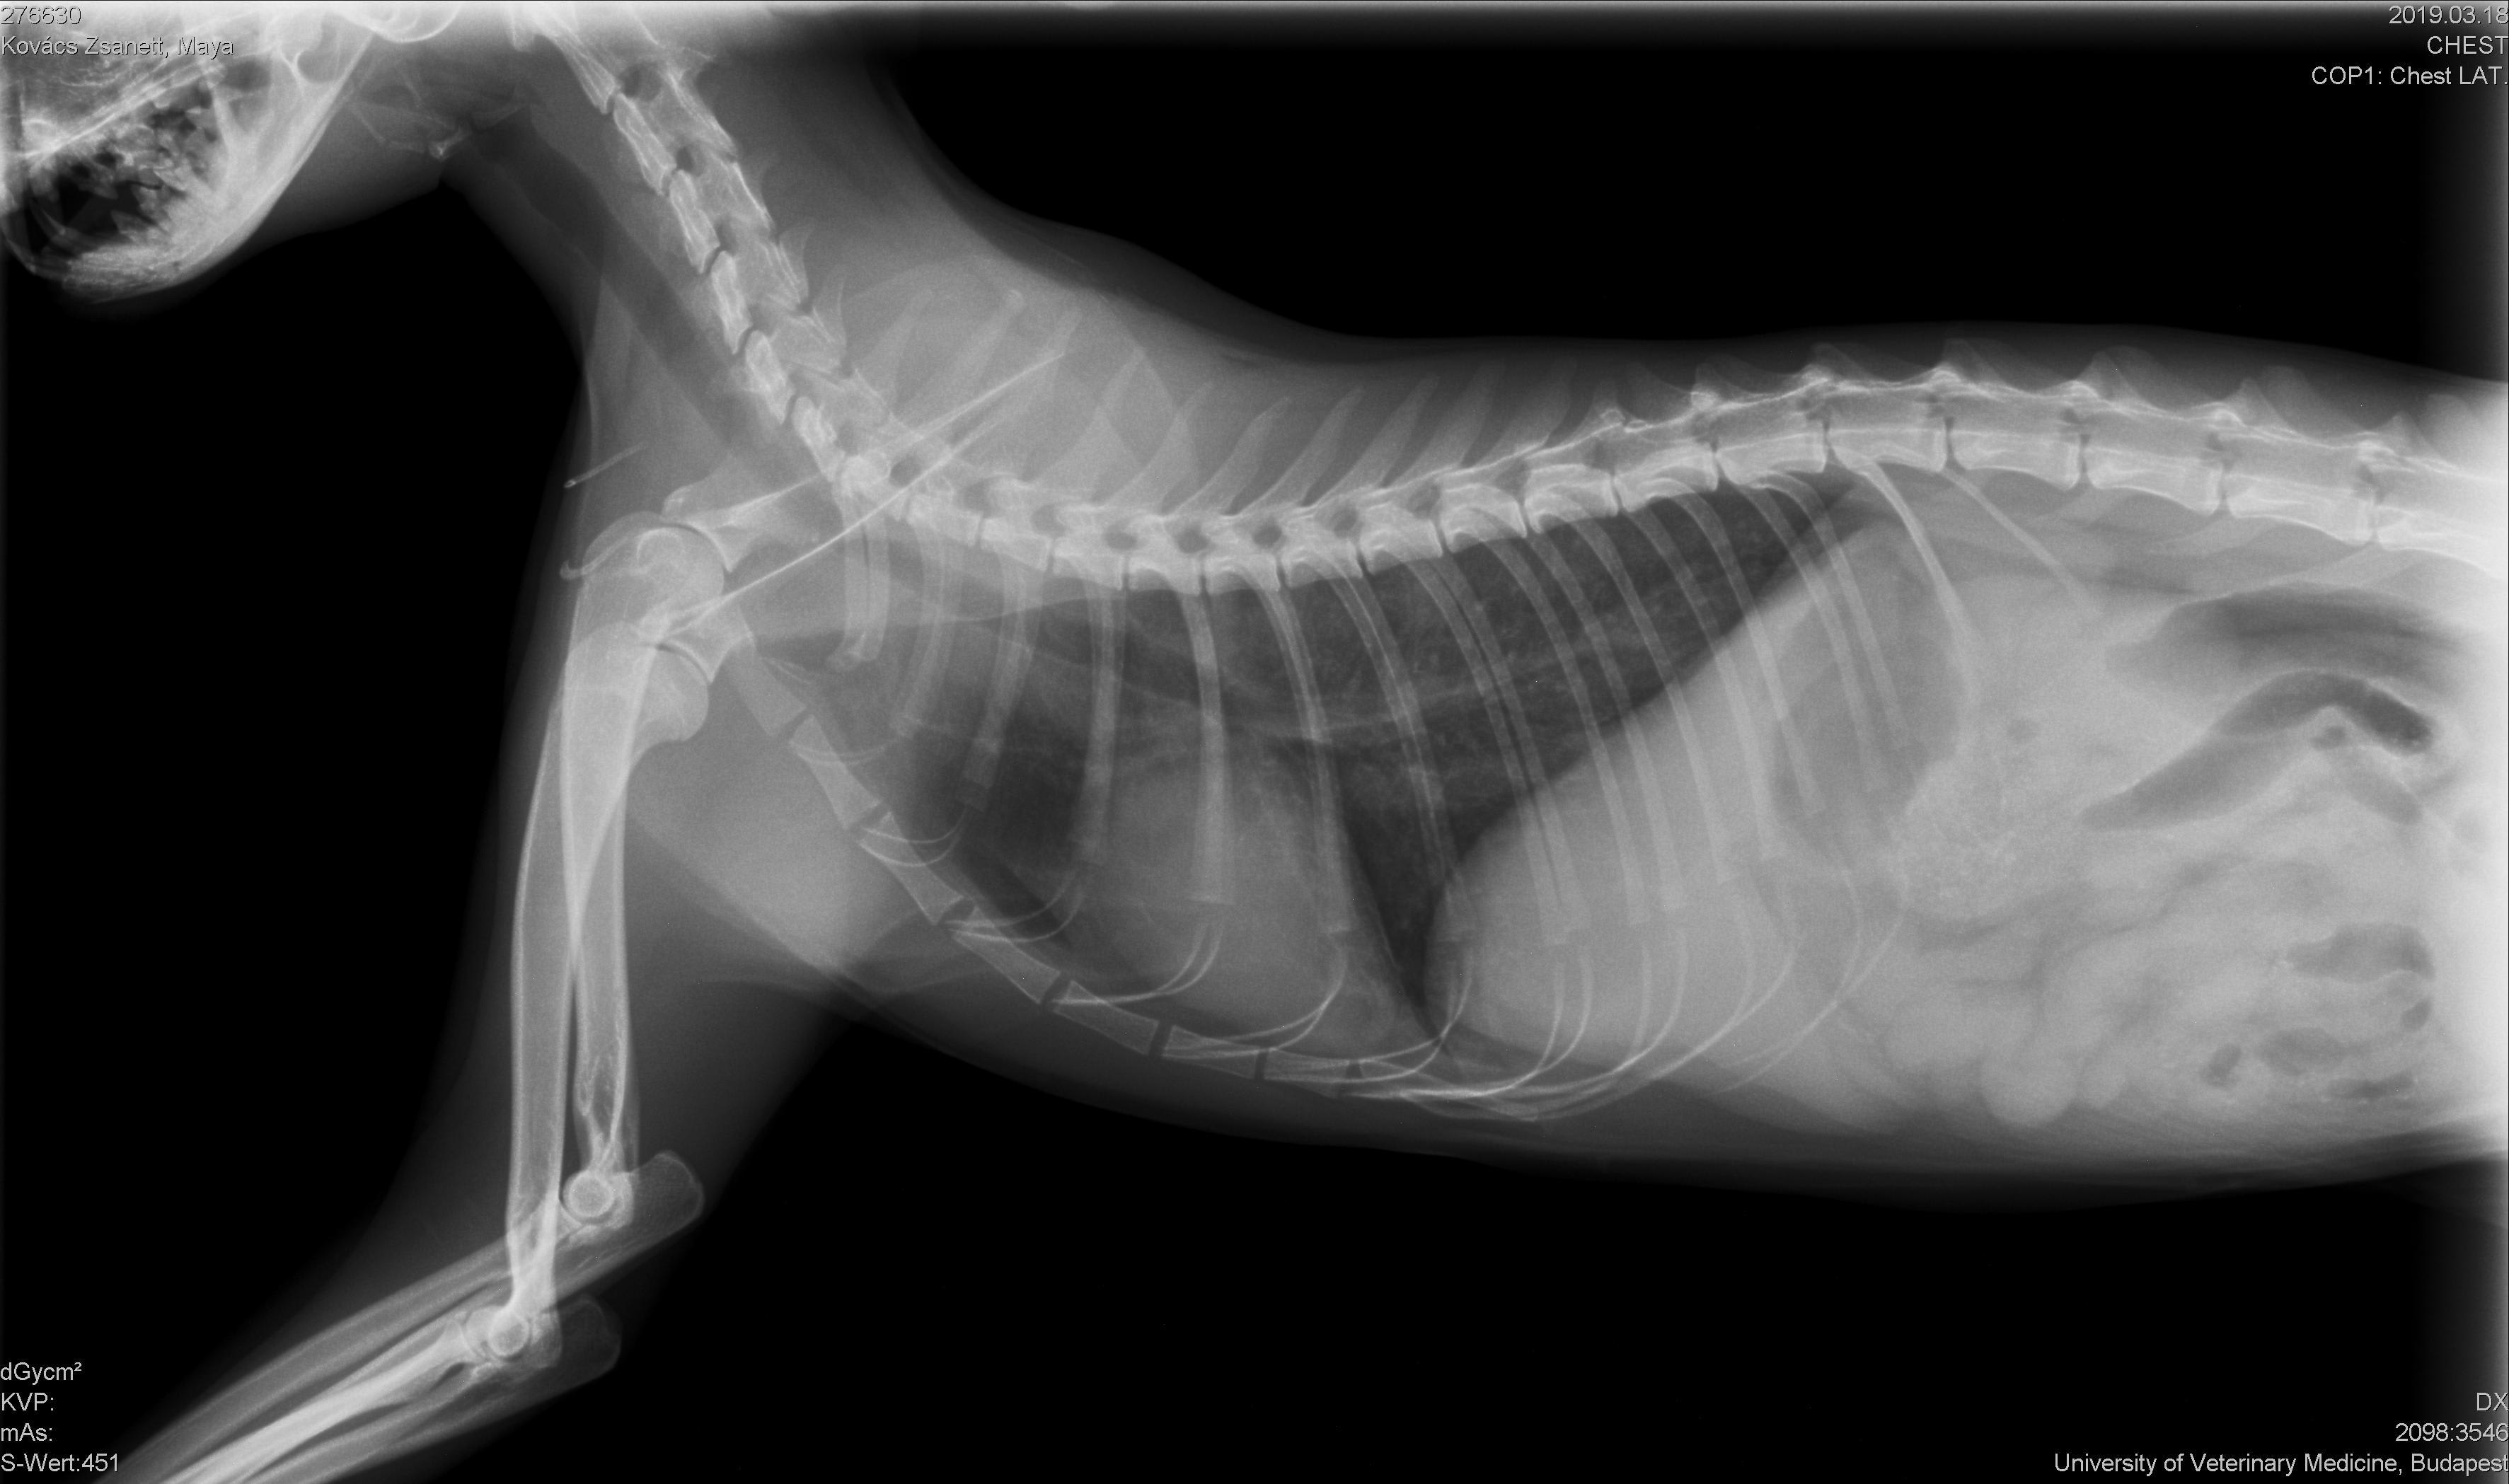

I have adopted a cat who has pulmonary fibrosis. The doctor advices to use Ventolin evohaler once a day. I wonder what else could I do for my cat. Are there any alternative holistic treatments or medicine for this disease? I attached the x-ray image of her lung. Is it really fibrosis? Yours sincerely, Nora Jakso

Although pulmonary fibrosis can happen in cats it is not as common as some other conditions and is very difficult to diagnose. There is no xray change that is specific for it and there is much overlap with other disease processes based on symptoms and xray findings. Ultimately it is a diagnosis from lung biopsy which is not typically performed due to the risk. It would also be quite unusual in such a young cat. Are you sure they don't mean feline asthma? If your cat is breathing well with intermittent symptoms this is likely not fibrosis. Unfortunately this site can not be used to provide a diagnosis as that would be illegal without an exam. But, what i would recommend is having good quality chest xrays sent to a radiologist for review. There needs to be 3 views taken and a diagnosis of anything should not be based on 1 image and should also take in to account the symptoms of the pet. I hope this helps and thank you for using Petco Pet Education Center, formerly Petcoach!